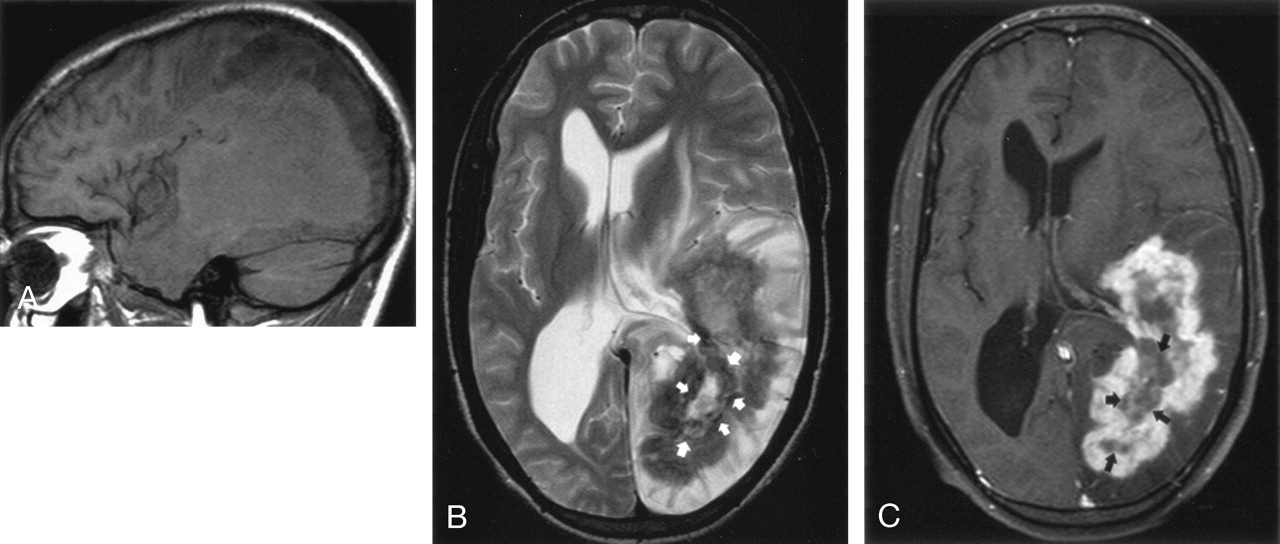

Brain MR imaging. A, Sagittal T1-weighted image shows the extent of the large mass, which is mostly isointense to gray matter with a mildly hyperintense perimeter. B, Axial T2-weighted image demonstrates the hypointense wall of the mass with surrounding brain edema. Thin, interrupted, low signal intensity zones (arrows) line the margin between the outer wall and central hyperintense necrotic area. C, Axial contrast-enhanced study reveals a thick, irregular enhancing rim. The low signal intensity zones (arrows) do not enhance.

CT of the brain revealed a large isoattenuated left temporoparieto-occipital mass measuring 8 × 4 × 9.5 cm with an irregular hypoattenuated center and surrounding brain edema (Fig 1). Small calcifications were present within the mass. The mass had a complex appearance on MR images (Fig 2). T2-weighted images revealed a thick hypointense perimeter and a heterogeneous hyperintense core. Margins of the lesion were well defined but irregular. On T1-weighted images, the mass was heterogeneous but mostly mildly isointense. A thick enhancing rim with a central nonenhancing portion was seen on postcontrast T1-weighted images. The T2 hypointense zone was thicker than the enhancing rim, which correlated with a very dark 2-mm band on the T2-weighted images along the inner margin of the enhancement (Fig 2B). Perilesional vasogenic edema and evidence of brain herniation were also depicted. A CT scan of the abdomen and pelvis revealed large bilateral psoas abscesses and bony destruction of the body of L2 and the spinous processes of L2 and L3. MR imaging demonstrated abnormal signal intensity and enhancement of the L2 and L3 spinous processes and L2–L3 disk space associated with a paravertebral soft tissue mass. No evidence of epidural abscess or spinal cord compression was seen. In light of the previous history of pulmonary tuberculosis, Pott’s disease was diagnosed. CT of the chest showed a right hilar mass encasing the right main bronchus and right pulmonary artery. Right upper-lobe consolidation and a few small middle-lobe pulmonary nodules were also present. CT-fluoroscopic guided drainage of the psoas abscesses was performed with drain placement 3 days after admission.

In the case of Yamada et al (8), the low signal intensity zone was found only at the junction of the internal nonenhancing cavity and the enhancing capsular wall on T2-weighted images. Similarly, we found a low signal intensity zone along the inner surface of the granuloma wall, but in addition, other scattered areas of hypointensity were present within central necrotic area. This apparent discrepancy can be explained by fragments of fungal growth breaking off from the low signal intensity zone.